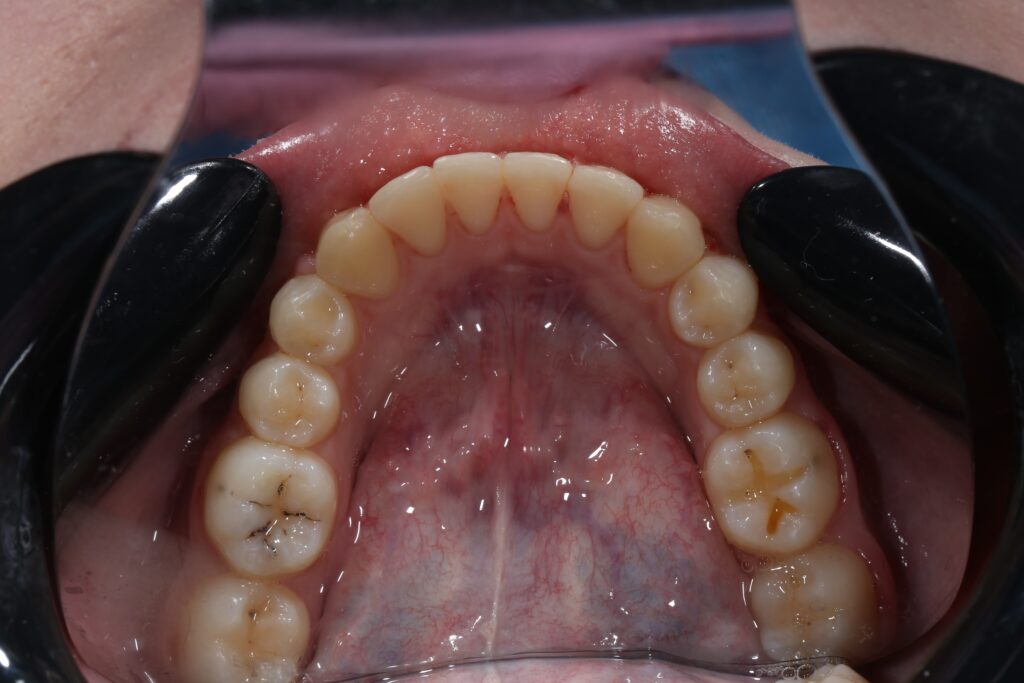

Результаты

результат лечения брекет-системой